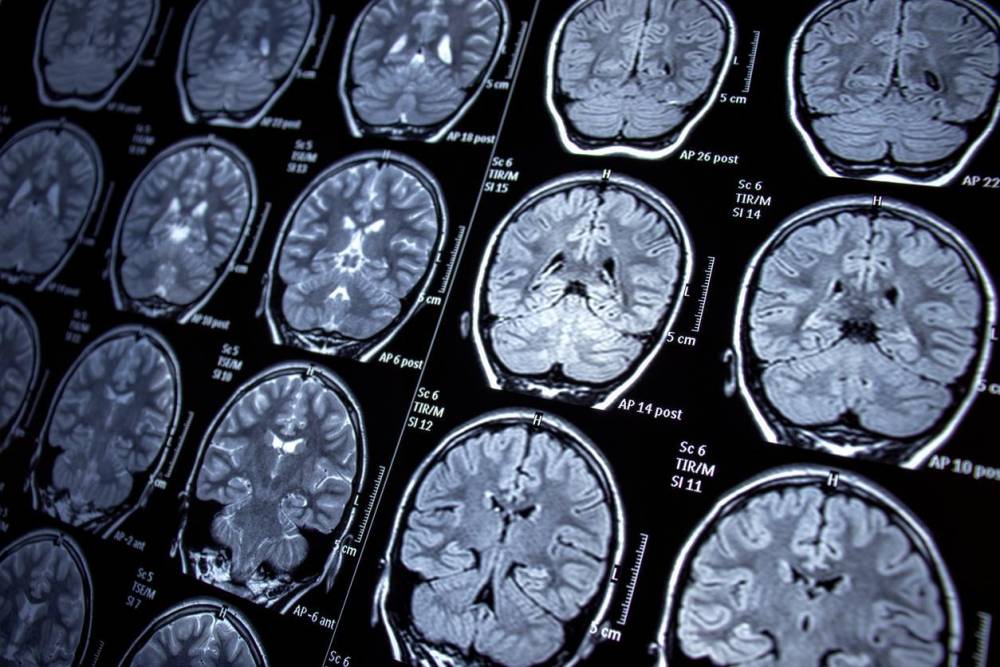

Une équipe de chercheurs de l’Institut national de la santé et de la recherche médicale (Inserm), de l’Université et du CHU de Lille a identifié pour la première fois l’implication des tanycytes dans l’apparition de la maladie d’Alzheimer.

Dans une étude récente publiée dans la revue scientifique Cell Press Blue, les scientifiques se sont intéressés au rôle de ces cellules situées dans l’hypothalamus. Les tanycytes sont déjà connus pour assurer des échanges entre le système sanguin et le liquide céphalorachidien (LCR), qui circule dans le cerveau. Les chercheurs ont cherché à comprendre leur implication dans le transport de la protéine Tau, un biomarqueur clé dans le diagnostic de la maladie d’Alzheimer.

Chez une personne en bonne santé, les neurones libèrent cette protéine dans le liquide céphalorachidien, avant qu’elle ne soit ensuite éliminée dans le sang. En revanche, chez les personnes atteintes de la maladie d’Alzheimer, la structure de Tau se modifie. D'après l'Inserm, elle ne remplit alors plus correctement sa fonction à l’intérieur des neurones et s’accumule sous une forme pathologique dans le cerveau. Cette accumulation perturbe progressivement le fonctionnement cérébral et entraîne la dégénérescence puis la mort des neurones, responsables du déclin cognitif caractéristique de la maladie.